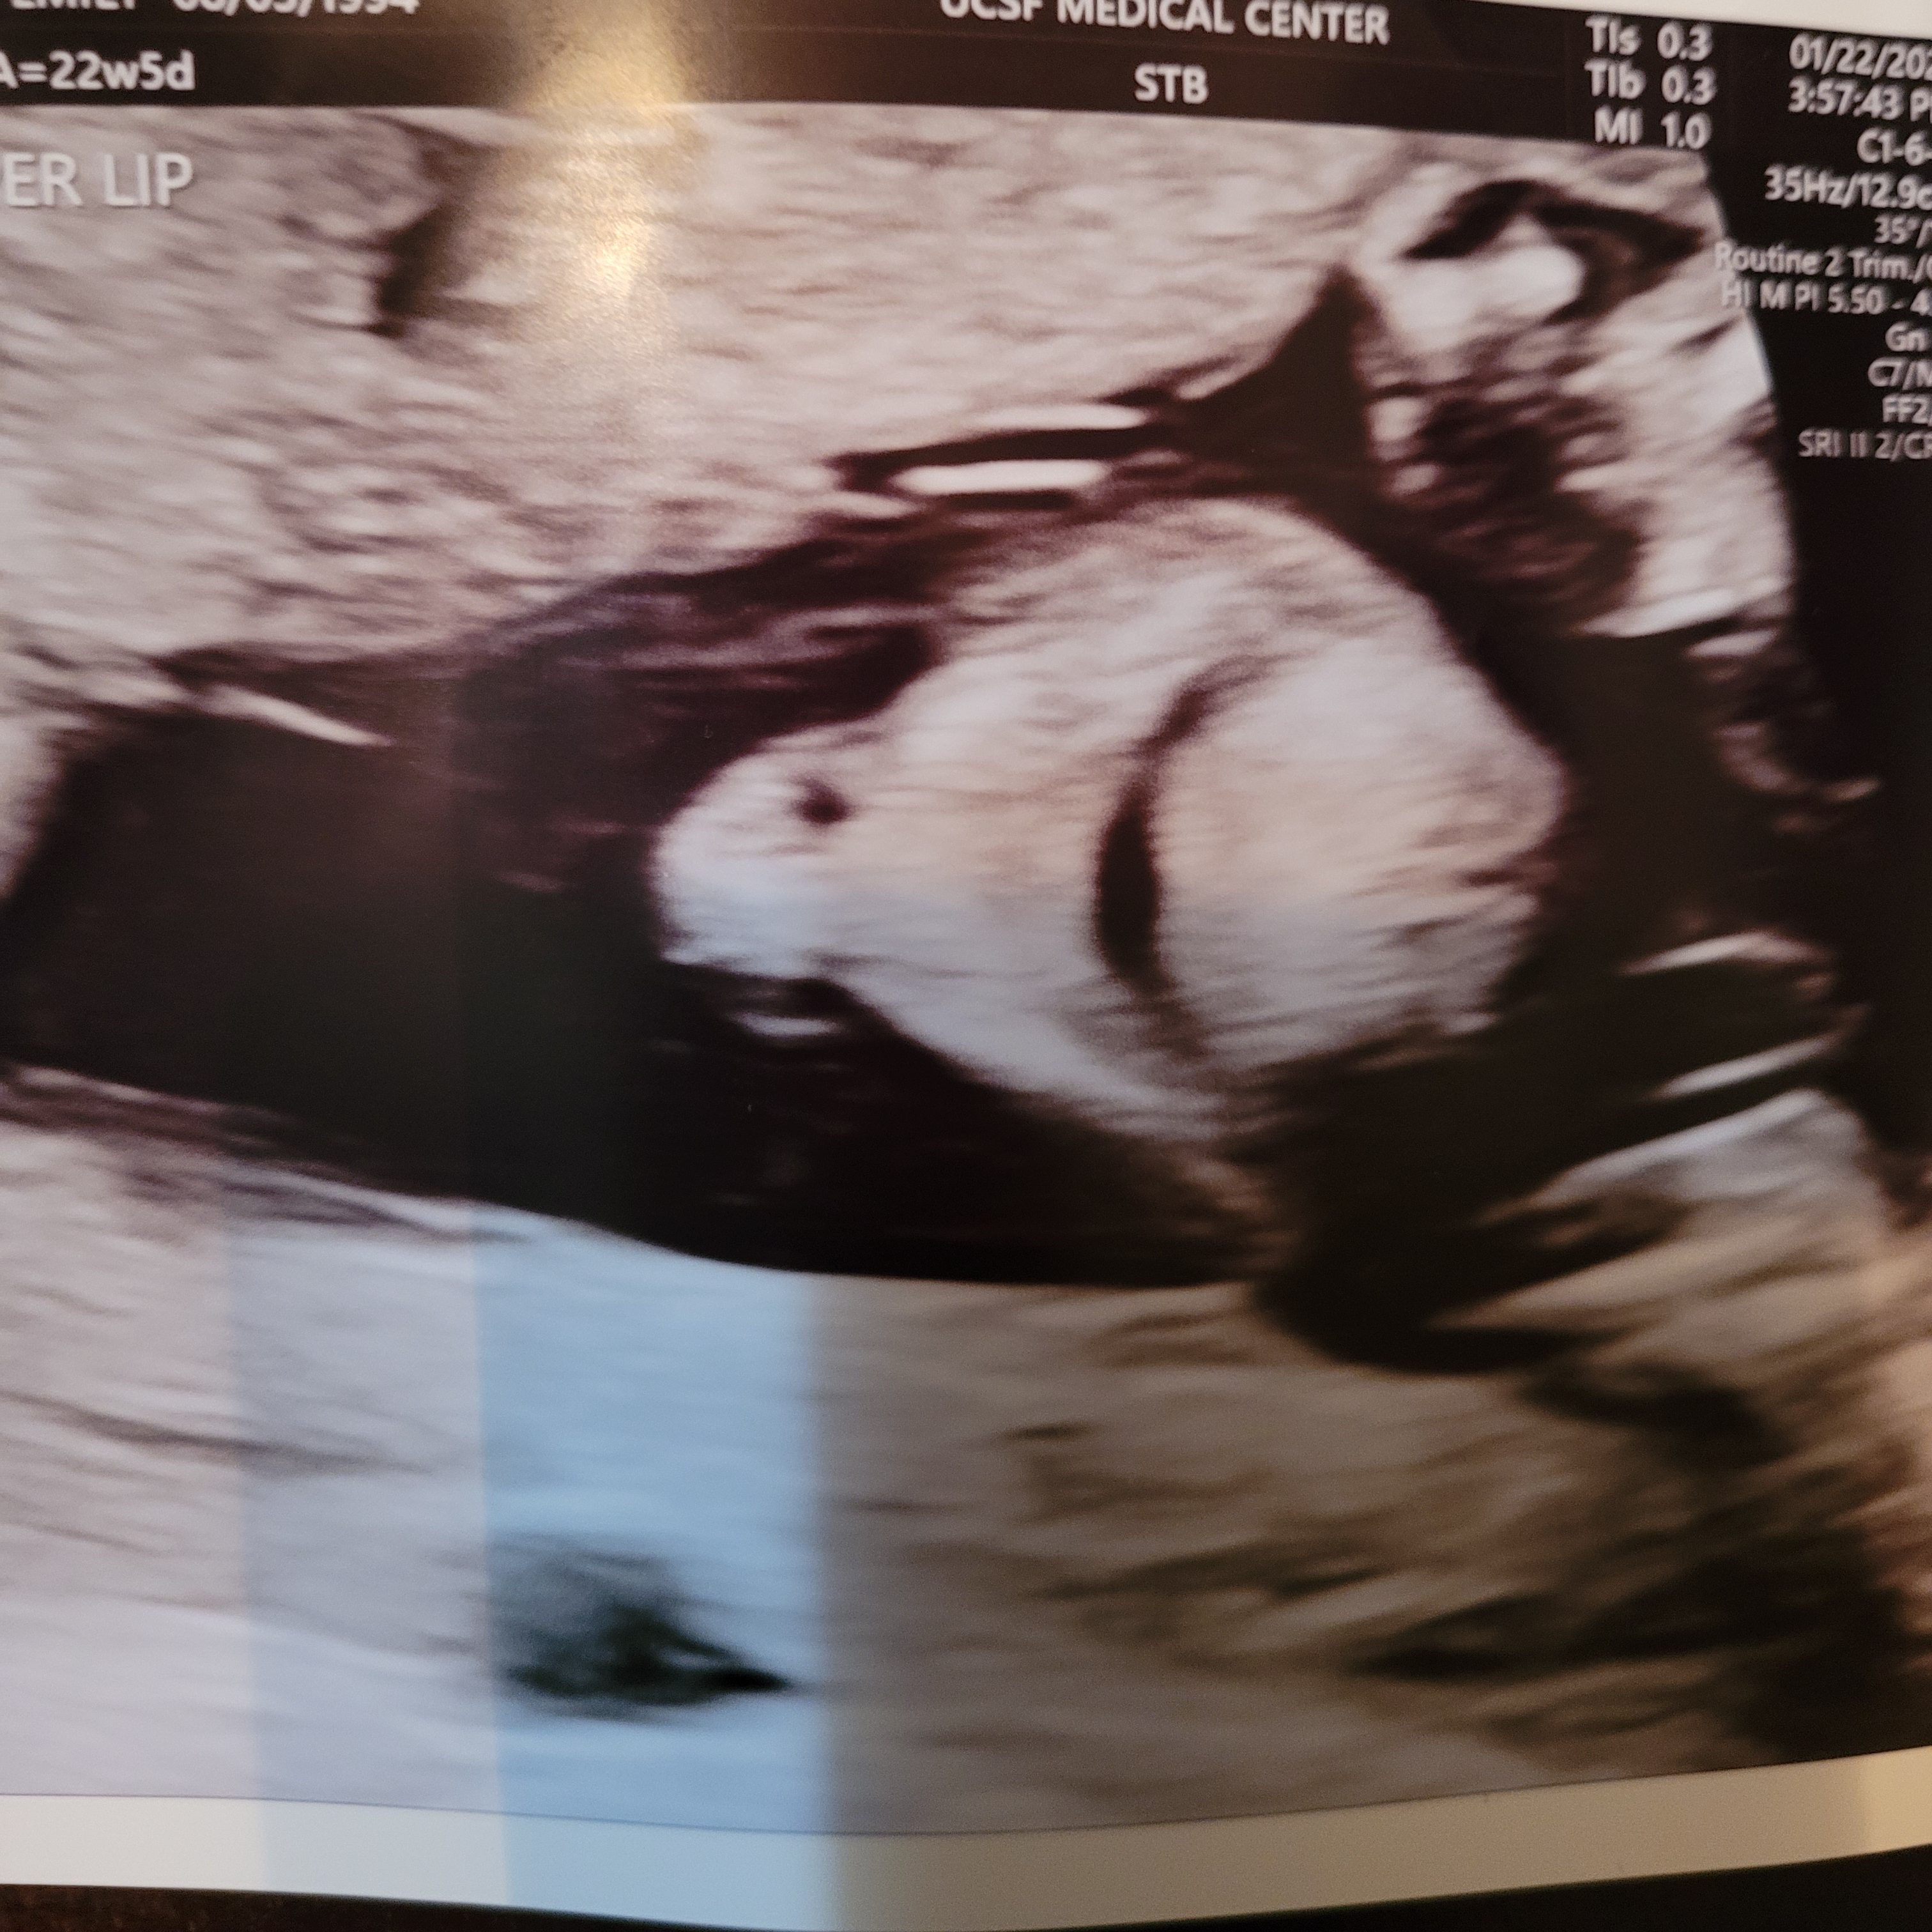

Last but most importantly: the anatomy ultrasound. During this hour-long appointment, the baby’s brain, heart, and spine are measured, and the toes and fingers counted to confirm they are all growing correctly.

The ultrasound tech commented repeatedly on the strange positions our baby was in, describing him first as a frog, with his legs pulled to his chest, and later as a taco, with his feet on either side of his head. So his nickname is now officially “taco-frog.”

We also got some pictures. My favorite is the one on the right that shows him covering his face with his hands, which is pretty cute. I think he looks a little like Emperor Palpatine too, but that is probably just me.